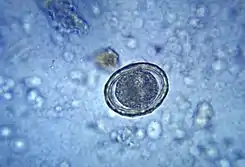

![]() Micrografía que muestra un huevo fertilizado de Ascaris lumbricoides | ||